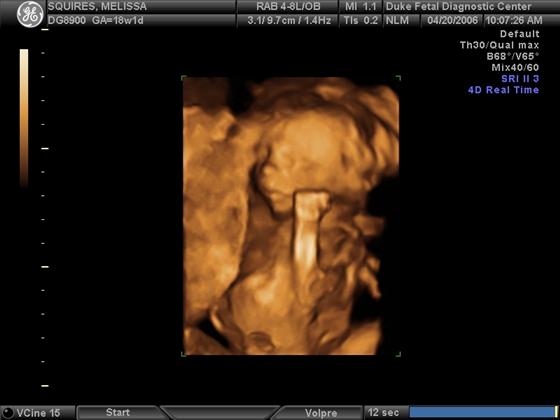

Pics from the 18 week sono...

He doesn't look as much of a skeleton that I thought he would!

1st pic profile pic of him yawning, 2nd pic is him in all of his glory, and the 3D pic. What do you think? Thanks! Image Attachment(s):

Wow, the 3D pic is amazing! Congrats